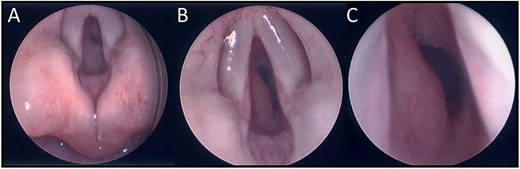

A 13-week-old child was acutely referred to the tertiary paediatric ENT team with stridor. The child had altered breathing for 2 weeks, initially treated as croup. On admission, the child had a tracheal tug, intercostal recessions and significant stridor. A 10 cm facial cutaneous plaque haemangioma was noted. Intravenous dexamethasone was commenced and micro-laryngoscopy showed a subglottic haemangioma occupying 40% of the airway, equivalent to Myer-Cotton classification Grade 1 (Fig. 1). Oral propranolol was commenced at 1 mg/kg/day in three divided doses as per local protocol increasing to 2 mg/kg/day once treatment was established. No neck lesion was apparent on clinical examination.

(A) Endoscopic (MLB) photographs of the supraglottic region. (B–C) Endoscopic (MLB) photographs of glottic and subglottic regions highlighting the presence of a subglottic haemangioma.